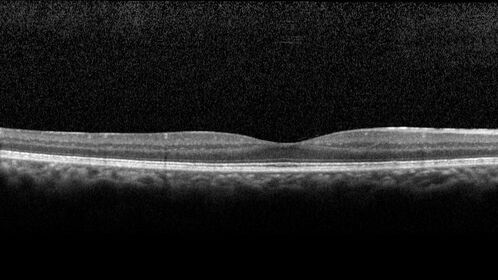

Ocular Lymphoma - Initially presented like auto-immune retinopathy

43 year old man: initial presentation - The vision in the left eye is blurry and opaque for about 2 weeks.  In the central of the vision, when he covers the right eye, in the center of the left eye there is a film with a light in the middle.  This has never happened before.  He has not been sick for the last few months.  A few weeks ago he saw waves on the floor when looking down but that has gone away.  Since the vision loss started the vision has not changed much.  The central vision is not getting better.

VA improved over 2 months to normal.  Then the patient had 2 more episodes of self-limited vision loss (no treatment).  Then 2 years later he presented with a diagnosis of CNS lymphoma and later developed subretinal deposits (last images)